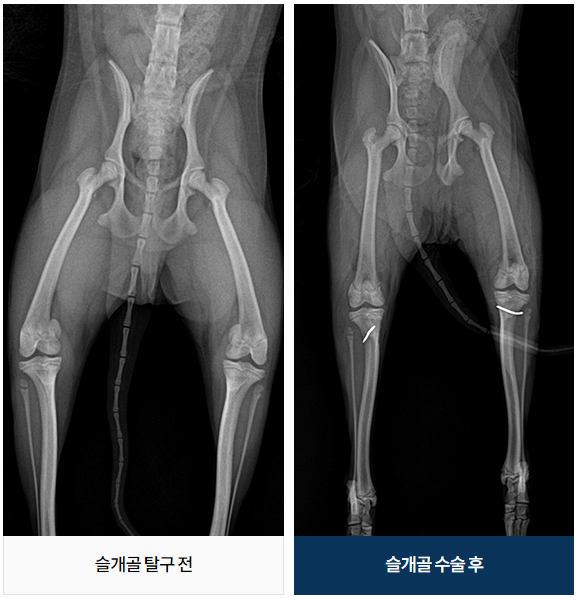

½½°³°ñ Å»±¸